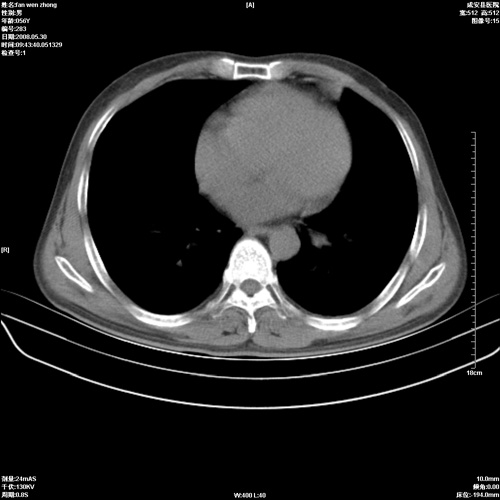

病人 男 56岁 一周前高热,体温达39-40度,经抗炎治疗后,体温渐降,达37,5-38度,轻微咳嗽,胸部不适 查白细胞为1.3万 行ct检查,请分析。

双肺内可见多发结节状病灶,并见小空洞,病人高热,白血球增高,应该是典型的迁徙性肺脓肿(多为金黄色葡萄球菌感染)。查一下口腔等其它部位有无感染灶。

双肺内可见多发结节状病灶,并见小空洞,病人高热,白血球增高,应该是典型的迁徙性肺脓肿(多为金黄色葡萄球菌感染)。建议治疗后复查.